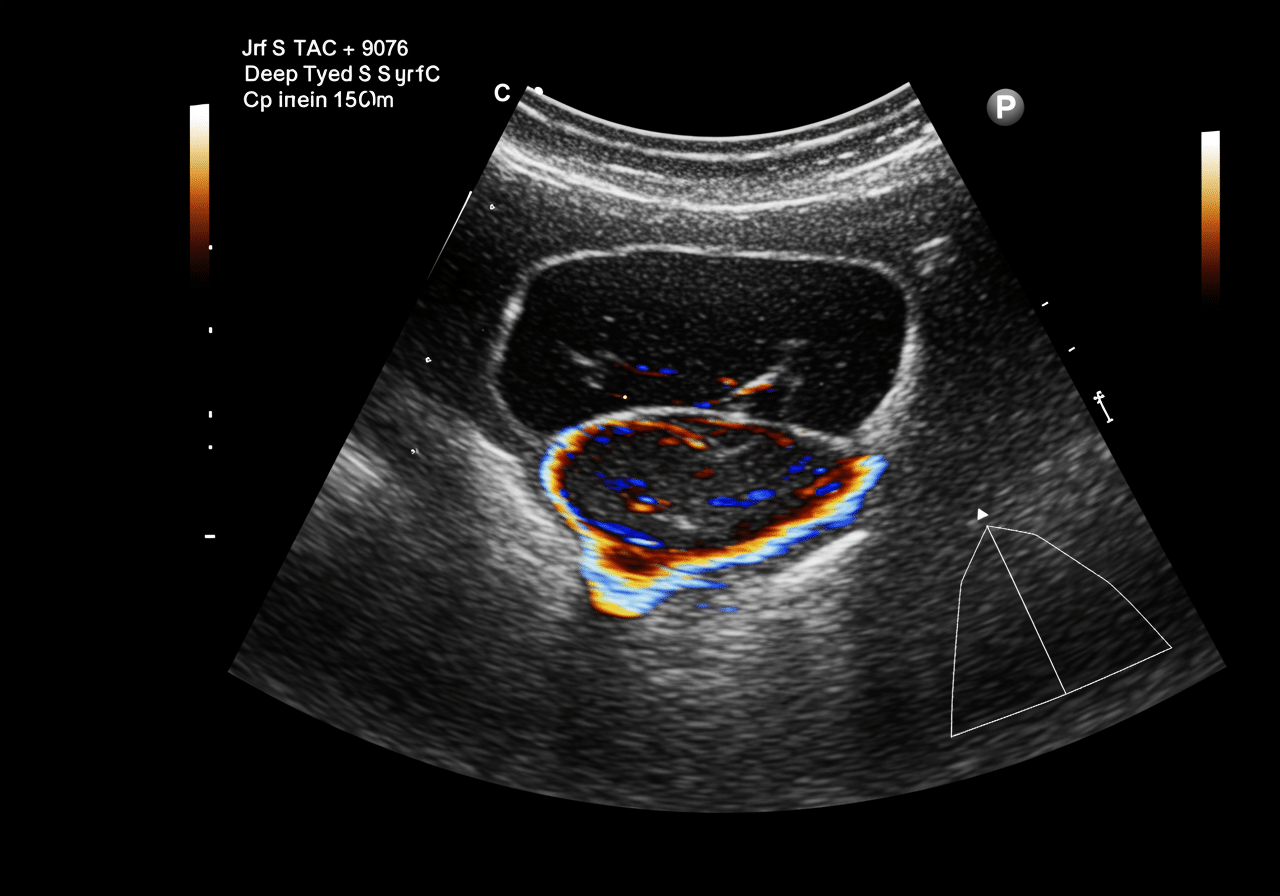

Advanced Vascular Doppler Technology: Beyond Basic Urgent Care

Priority ER's diagnostic capabilities for vascular doppler ultrasound for deep-vein thrombosis exceed Joint Commission standards for emergency departments[14], featuring equipment typically found only in specialized vascular centers. Our duplex doppler system produces images with 30% better resolution than standard urgent care facilities, enabling detection of small thrombi, valve incompetence, and venous obstruction as subtle as 1mm[15]. The integration of PACS (Picture Archiving and Communication System) technology allows instant image transmission to consulting vascular surgeons when complex DVT requires specialized anticoagulation planning.

Advanced imaging through our 64-slice CT scanner provides three-dimensional venous reconstruction within minutes, crucial for identifying clot extent, pulmonary embolism risk, and treatment requirements that standard doppler cannot fully assess. For chest pain cases with leg swelling, our digital imaging system captures both pulmonary and venous studies simultaneously, reducing radiation exposure by 40% while providing comprehensive thrombosis evaluation. This technology gap explains why the American College of Emergency Physicians recommends freestanding ERs over urgent care for all suspected DVT and serious vascular emergencies requiring immediate diagnostic imaging.

Our vascular-trained staff ensures comfortable doppler experiences with minimal anxiety. The process takes 15-25 minutes and is completely painless - you simply lie still while the sonographer applies gel and moves the transducer along your leg to visualize blood flow. Our vascular emergency specialists use advanced color-flow imaging and compression techniques, with immediate physician interpretation following ACEP guidelines.